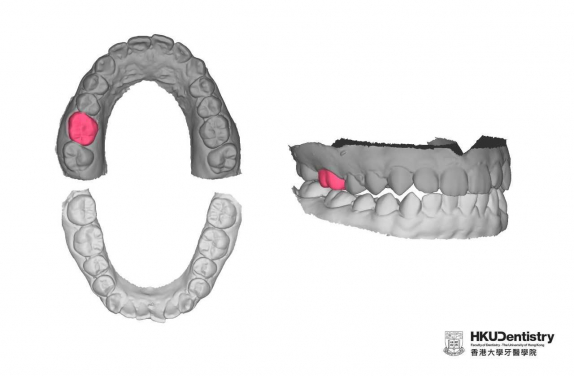

Photo 2: The research team uses 3D GAN to learn the relationship of teeth in a dental arch on the 175 student participants. After training, 3D GAN is able to generate a tooth (red) based on the feature of remaining teeth (dark grey). Research team proposes further investigate the presence of opposing teeth helps the AI to generate a more natural tooth (red).

The AI technology used in the process was based on 3D Generative Adversarial Network (3D-GAN) algorithm and tested on 175 participants recruited at HKU. The study shows that AI technology could reconstruct the shape of a natural healthy tooth and automate the process of false teeth design with high accuracy.

“The 3D GAN algorithm was selected due to its superior performance on 3D object reconstruction compared to other AI algorithms. In the preliminary study, 3D GAN was able to rebuild similar shapes to the original teeth for 60% of the cases. It is expected to mature with more AI training data,” co-Investigator, Dr Reinhard Chau explained.

The new approach only requires the digital model of a patient’s dentition to function. It can learn the features of an individual’s teeth from the rest of the dentition and generate a false tooth that looks like the missing tooth.